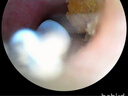

这款Bebird蜂鸟可视挖耳勺简直是洁耳神器!星空 蓝配色高级有质感。最惊喜的是高清可视功能,连耳 道细节都看得一清二楚,终于能安心掏耳朵了。自带 多种专业镊头,轻松夹出顽固耳垢,全程就像在给自 己做采耳SPA。操作简单,连接手机App还能录像, 清洁过程变得特别治愈。材质亲肤安全,使用感舒适 不会痛。从此告别盲掏时代,绝对是提升生活幸福感 的好物,相见恨晚!

还不错,快递很快,产品也还好,能很清楚的看见耳朵里的情况,最近耳朵里结痂了,这个看的非常清楚,操作也方便,下个软件连上Wi-Fi就OK了

可视挖耳勺:安全又解压的掏耳神器 这把可视挖耳勺彻底终结了“盲掏”时代,堪称提升生活幸福感的小物!连接手机APP超便捷,WiFi秒连不卡顿,高清镜头搭配环绕灯光,耳道里的细小耳垢、绒毛都看得一清二楚。 最贴心的是软硅胶耳勺头,触感柔软亲肤,碰到耳道壁也完全不疼,还送了好几个替换头,全家共用也卫生。自带的安全刻度能控制入耳深度,给孩子掏耳朵再也不用提心吊胆。 用完后清理简单,续航也很持久。每次精准清理完耳道,那种清爽感太解压了,再也不用依赖采耳店,在家就能轻松做耳部护理,性价比超高!

家人们,这款蜂鸟可视掏耳勺太绝啦!高清摄像头让耳道情况一目了然,挖耳更精准安全。操作简单,拿着顺手。灯光亮度合适,不会刺眼。之前总担心挖不干净还怕伤耳朵,有了它全解决。用了一段时间,真的好用,必须好评!

之前买过这个牌子的挖耳勺,也买过其他几种牌子的,同价位的话还是这家的质量要相对好一点,不论从手感、紧实度还是wifi连接的稳定性流畅度都很不错。

售后好,有质量问题给退换,不麻烦。画面清晰,冬天使用不冻手